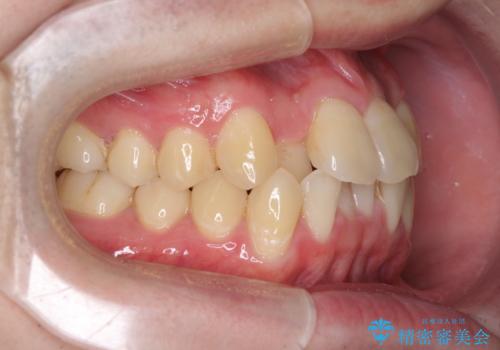

前歯のクロスバイト インビザラインによる矯正治療

- 上下のクロスバイトと前歯のデコボコを気にして来院された患者様です。

インビザラインを用い、IPR(歯と歯の間を削る)と歯列全体を拡大させることで、歯並びを整えていくこととしました。

上下ともに歯列全体を後方に移動させるため、上下の親知らずを抜歯することとしました。

奥に位置していた上の前歯が下の前歯を乗り越える際、奥歯でものを咬むことができず、辛い時期が続きました。